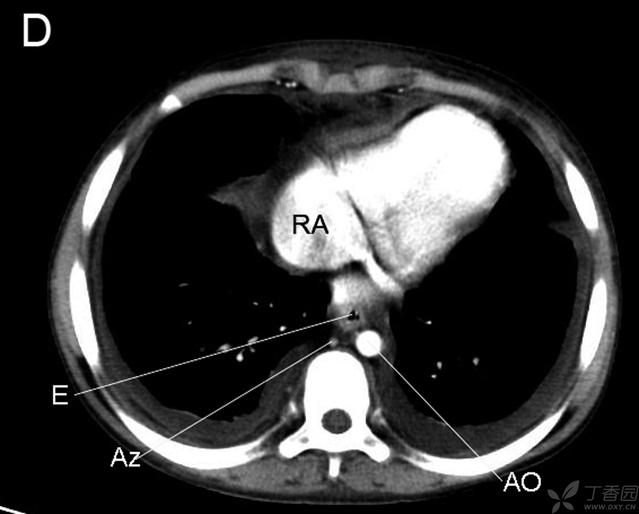

RB右支气管 LA左房 LB左支气管 E食管 AZ奇静脉 AO主动脉

RA右房 RV右室 LA左房 LV左室